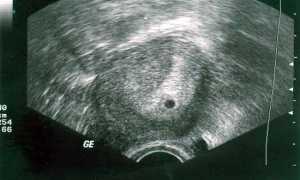

- Признаки эндометриоза у женщин – первые проявления заболевания и диагностика